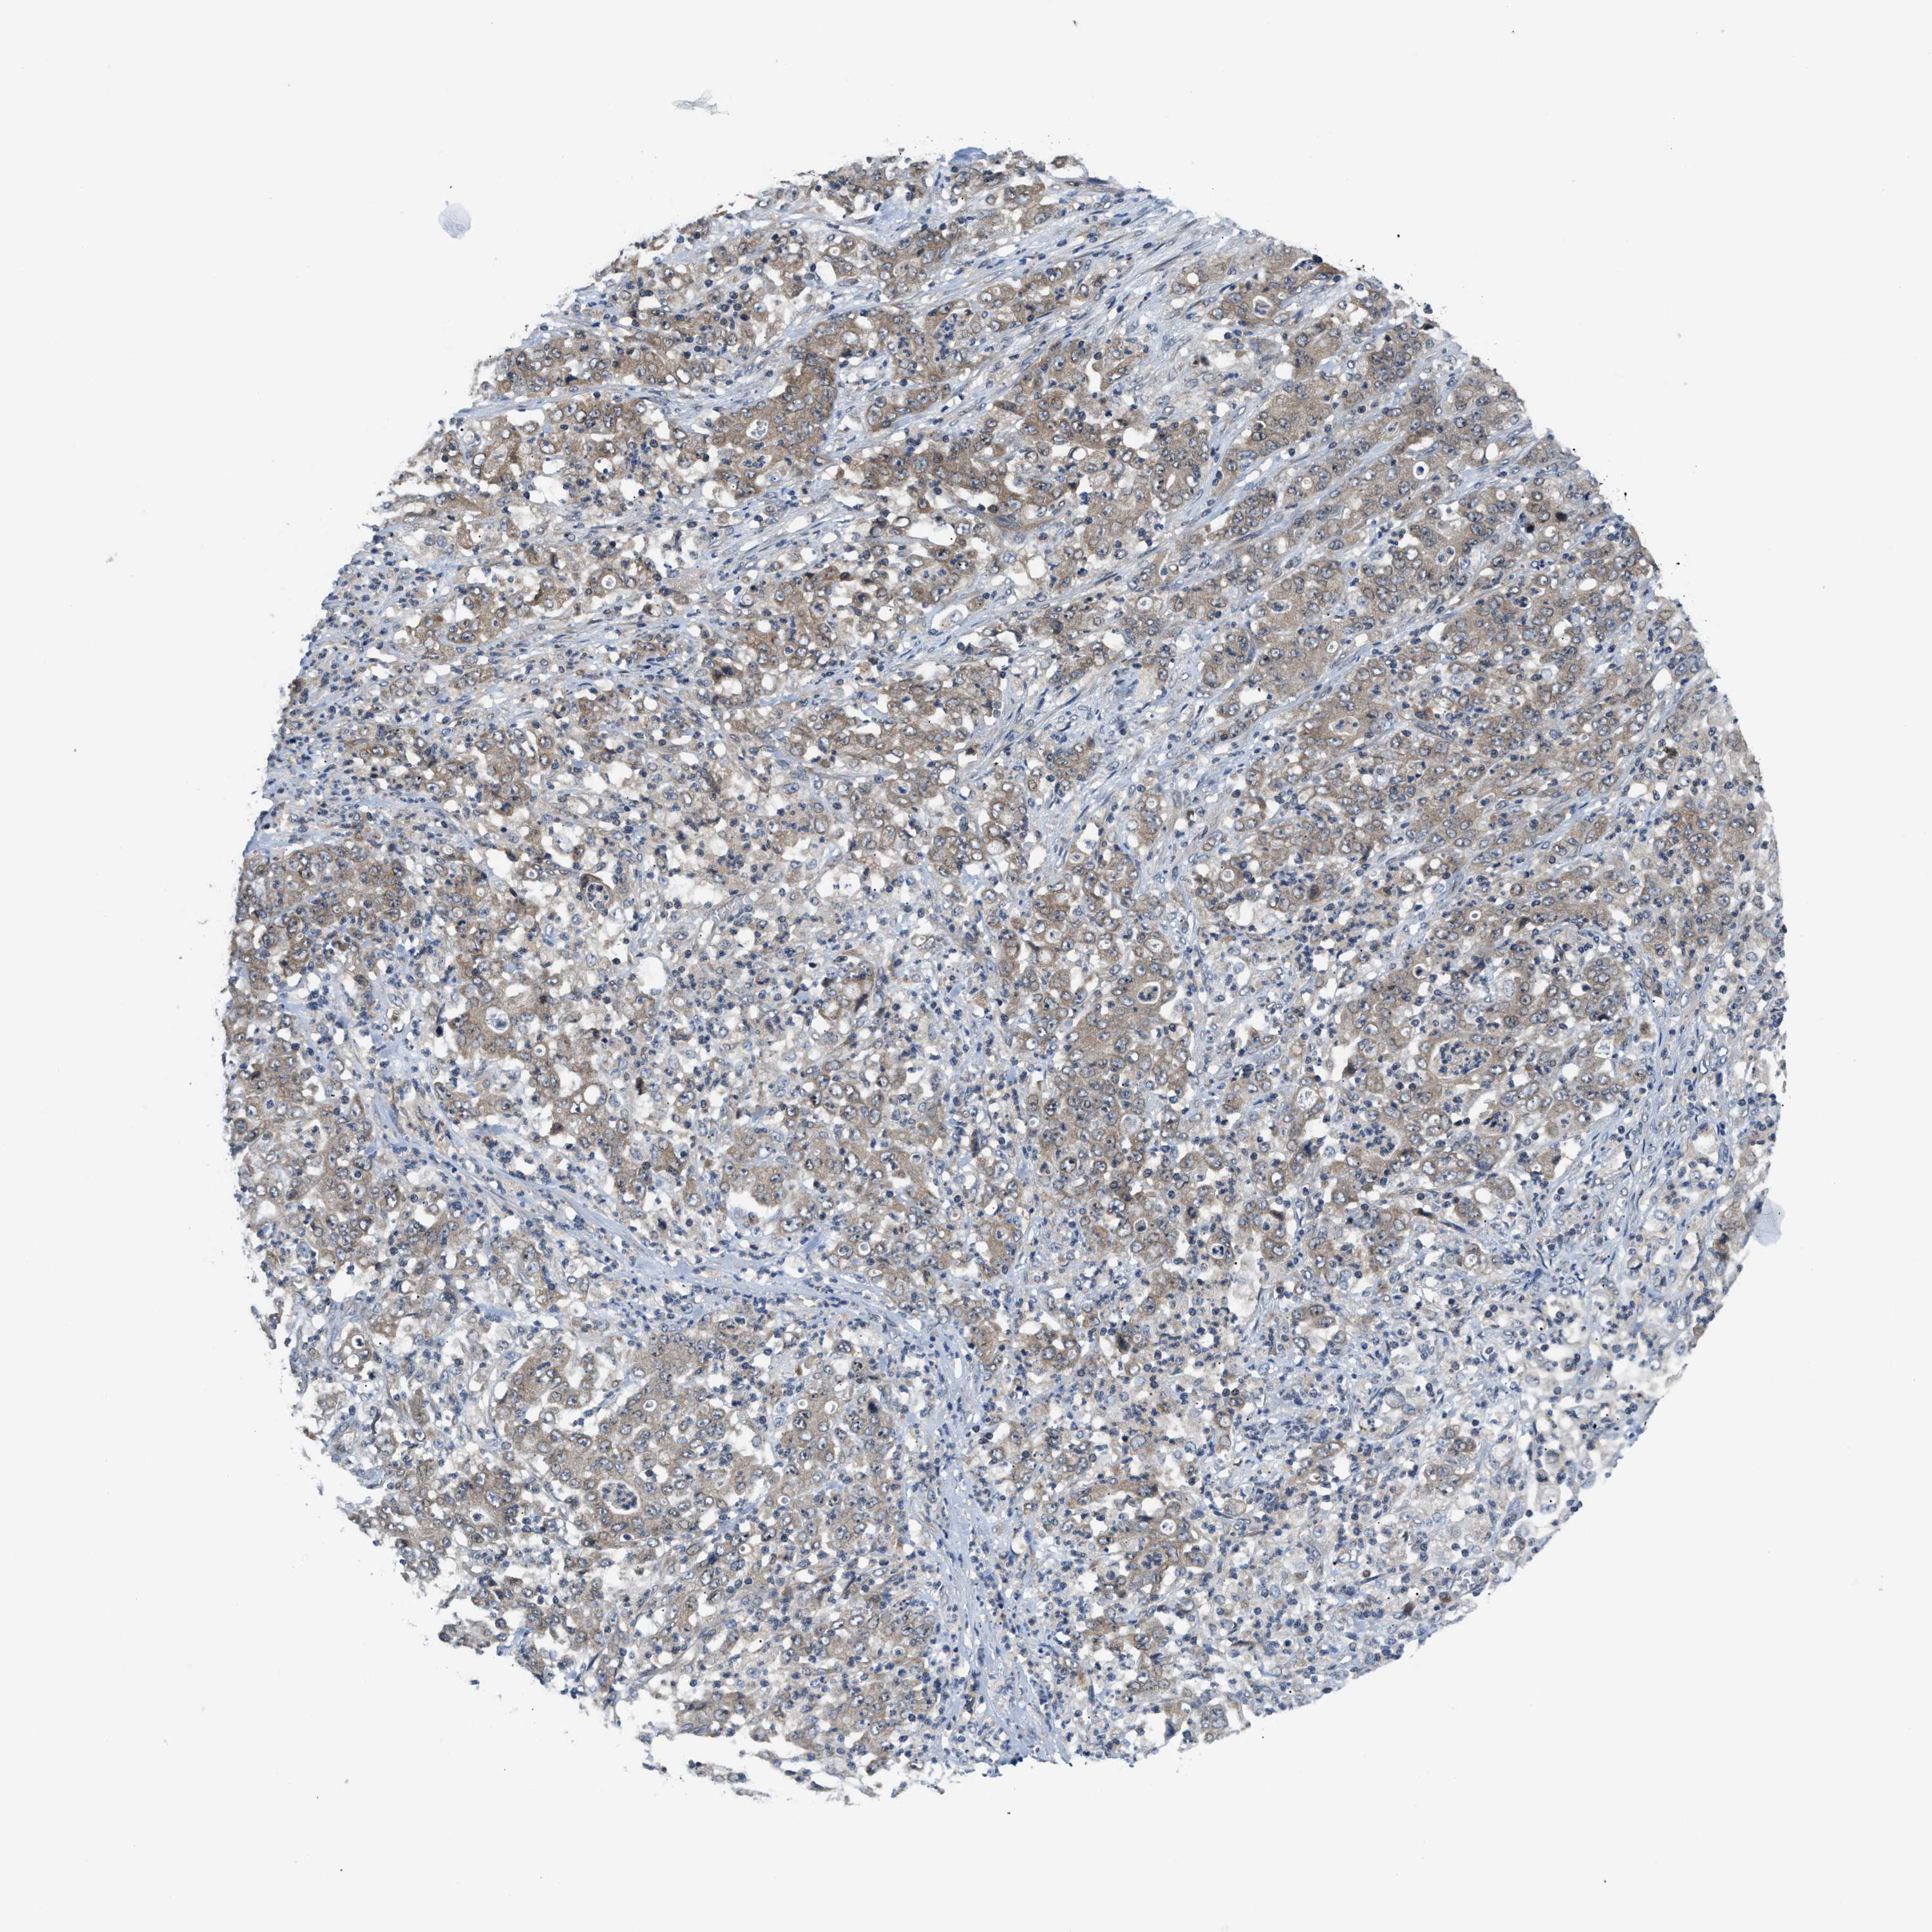

STOMACH CANCER - Protein expressioni

A mouse-over function shows sample information and annotation data. Click on an image to view it in a full screen mode. Samples can be filtered based on level of antibody staining by selecting one or several of the following categories: high, medium, low and not detected. The assay and annotation is described here.

Note that samples used for immunohistochemistry by the Human Protein Atlas do not correspond to samples in the TCGA dataset.

Antibody stainingi

Antibody staining in the annotated cell types in the current human tissue is reported as not detected, low, medium, or high, based on conventional immunohistochemistry profiling in selected tissues. This score is based on the combination of the staining intensity and fraction of stained cells.

Each image is clickable and will lead to virtual microscopy that enables deeper exploration of all samples and also displays staining intensity scores, fraction scores and subcellular localization as well as patient and tissue information for each sample.

Antibody HPA026303

Antibody CAB020822

Staining

High

Medium

Low

Not detected

Intensity

Strong

Moderate

Weak

Negative

Quantity

>75%

75%-25%

<25%

None

Location

Nuclear

Cytoplasmic/membranous

Cytoplasmic/membranous,nuclear

Adenocarcinoma, NOS

Adenocarcinoma, High grade